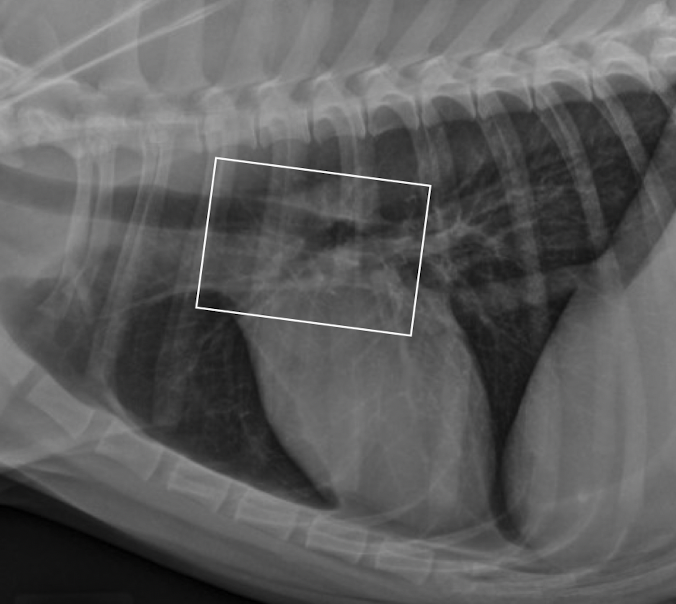

which one pulmonary mass vs extrapleural sign

A

extrapleural sign: